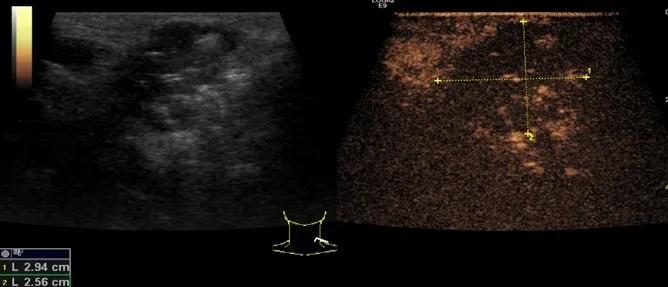

第5例是乳腺癌的患者,右乳恶性肿瘤术后化疗后1年出现淋巴结转移,患者基本情况差,拒绝放化疗,行局部热消融后也实现充盈缺损,术后一个月强化信号消失。

(病例5图例)